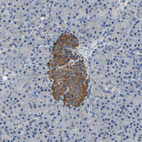

Immunohistochemical staining of human skeletal muscle shows strong cytoplasmic positivity in myocytes.